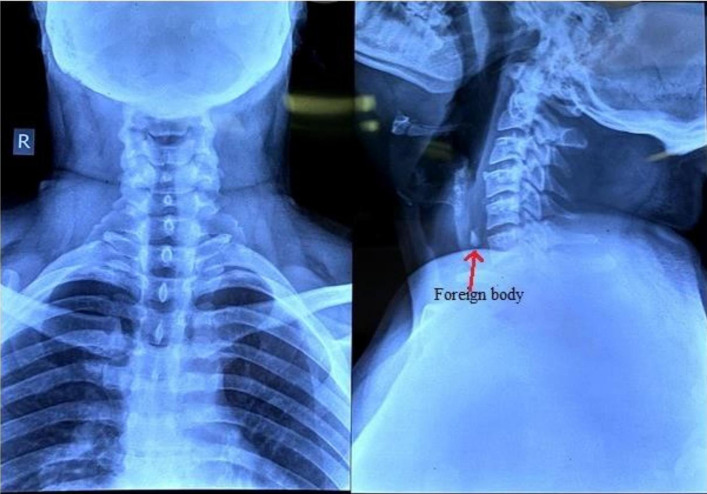

Antero-posterior, lateral neck and upper chest plain radiograph (Fig. 1) revealed the presence of a radio-opaque foreign body in the upper cervical oesophagus at the level of 5th and 6th cervical vertebra.

Fig. 1.

Anteroposterior and lateral view of neck and chest showing radio opaque foreign body in the oesophagus at the level of 5th and 6th vertebra